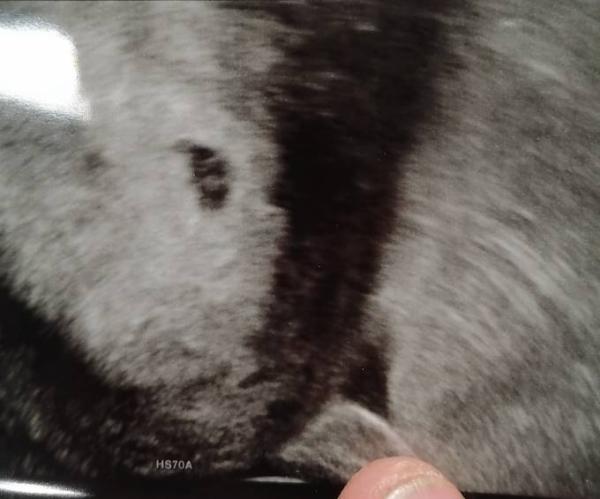

Heute hatte ich ultraschall, es waren 2 einer hat es leider nicht geschafft dafĂŒr der eine KrĂŒmmel bin jetzt 6 ssw. Fruchthohle dotter Sack zusehen. NĂ€chste Woche dann hin zum schaun ob das Herz schlĂ€gt Mir geht's nicht so gut sehr mĂŒde Übelkeit muss aber auch viele medis nehmen.

Bild zu Gute Nachricht und traurige 😱 - Kinderwunschbehandlung